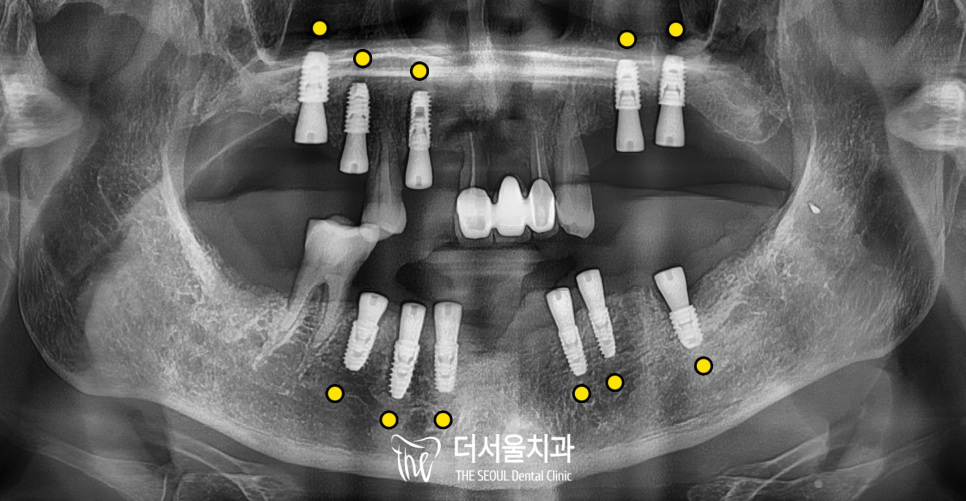

우선, 3D 스캔을 활용하여

모의식립을 진행하였습니다.

치조골 전반에 걸쳐 고정체가 식립되기에는

두께, 길이, 밀도가 충분하지 못한 경우가 많고

염증 조직이 제거된 자리에

뼈이식(GBR) 추가 보강이 필요하다는 소견입니다.

mm단위까지 시뮬레이션을 섬세하게 마친 후

본격적인 치료를 진행했습니다.

모의시술대로 뼈를 보강하며

11개의 고정체를

정확한 자리에 심어드렸습니다.

그리고 치은의 회복과 모양 형성을 돕는

힐링 어버트먼트를 체결해드렸습니다.